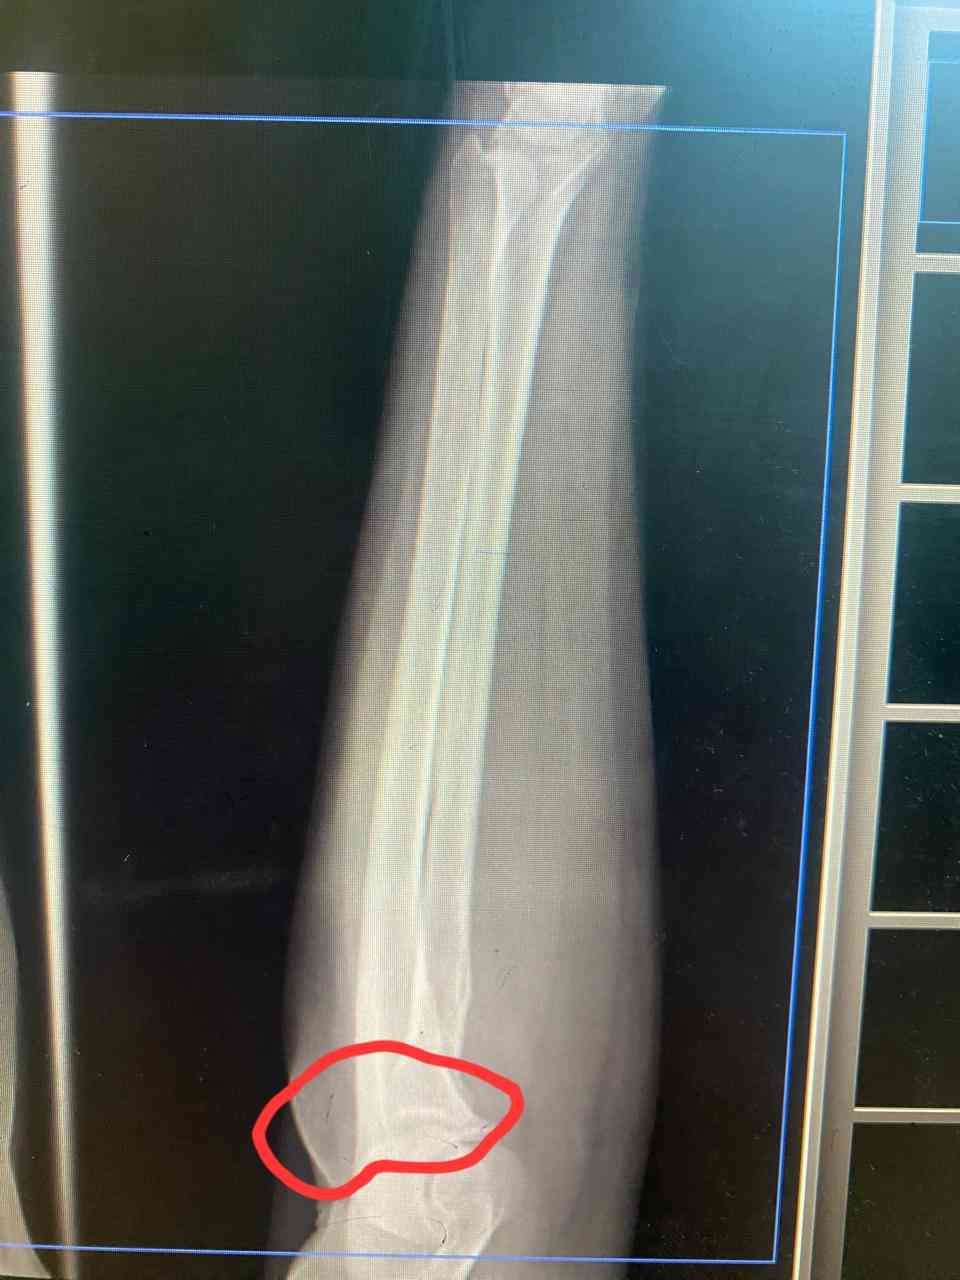

صورة شعاعية لمرفق اليد

لدي تورم عند المرفق مع وجع تم إرفاق صورة شعاعية لمرفق اليد

الصوره غير واضحه -من الافضل مراجعة طبيب روماتيزم للفحص السريري لاجراء اللزم وخاصه ESR CRP RF , واخرى حسب الفحص السريري 0 2025-10-27T07:37:29+00:00 2025-10-27T07:37:29+00:00

الصوره غير واضحه -من الافضل مراجعة طبيب روماتيزم للفحص السريري لاجراء اللزم وخاصه ESR CRP RF , واخرى حسب الفحص السريري